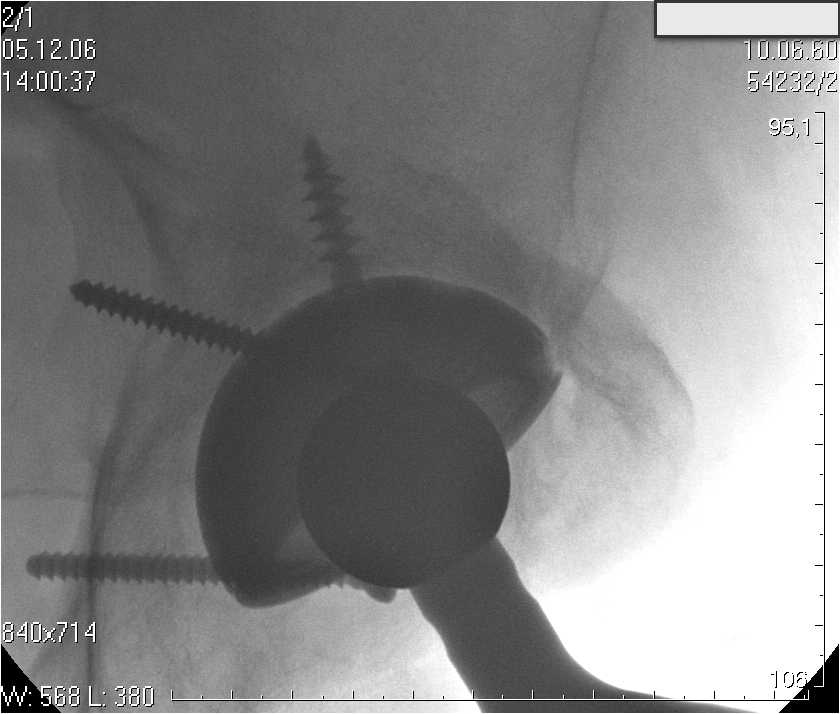

Нестабильность вертлужного компонента эндопротеза

Глубокие и поверхностные вены нижних конечностей проходимы. Умеренная недостаточность клапанов подколенных вен. Данных за тромбоз глубоких вен на момент осмотра не получено. А вот что пишет наш рентгенолог: На серии рентгенограмм области левого тазобедренного сустава определяется тотальный бесцементный эндопротез. Вокруг тени чашки эндопротеза определяется ободок остеорезорбции. Кроме того, визуализируется деформированный костный винт фиксирующий консолидированный отломок вертлужной впадины, вплотную прилегающий к тени чашки эндопротеза. Заключение: Рентгеновские признаки нестабильности чашки тотального эндопротеза. Лучевая нагрузка: 6 мЗв.

У нас в отделении разошлись мнения: начальник мой утверждает, после сравнения снимков, принесенных больным от августа и октября 2006года и наших рентгенснимков, что у больного нет нестабильности вертлужного компонента, и что надо назначит курс консервативной терапии: препараты кальция, миакальцик, увеличить осевую нагрузку на левую нижнюю конечность, ЛФК направления на укрепление мышц бедра, ягодиц, физиолечение. А я утверждаю, что у больного клиника нестабильности вертлужного компонента, и необходима ревизия вертлужного компонента, не исключено даже наличие инфекции под чашкой эндопротеза (не смотря на отсутствие клинических признаков инфекции). В результате проводимой консервативной терапии, боли у больного усилились.